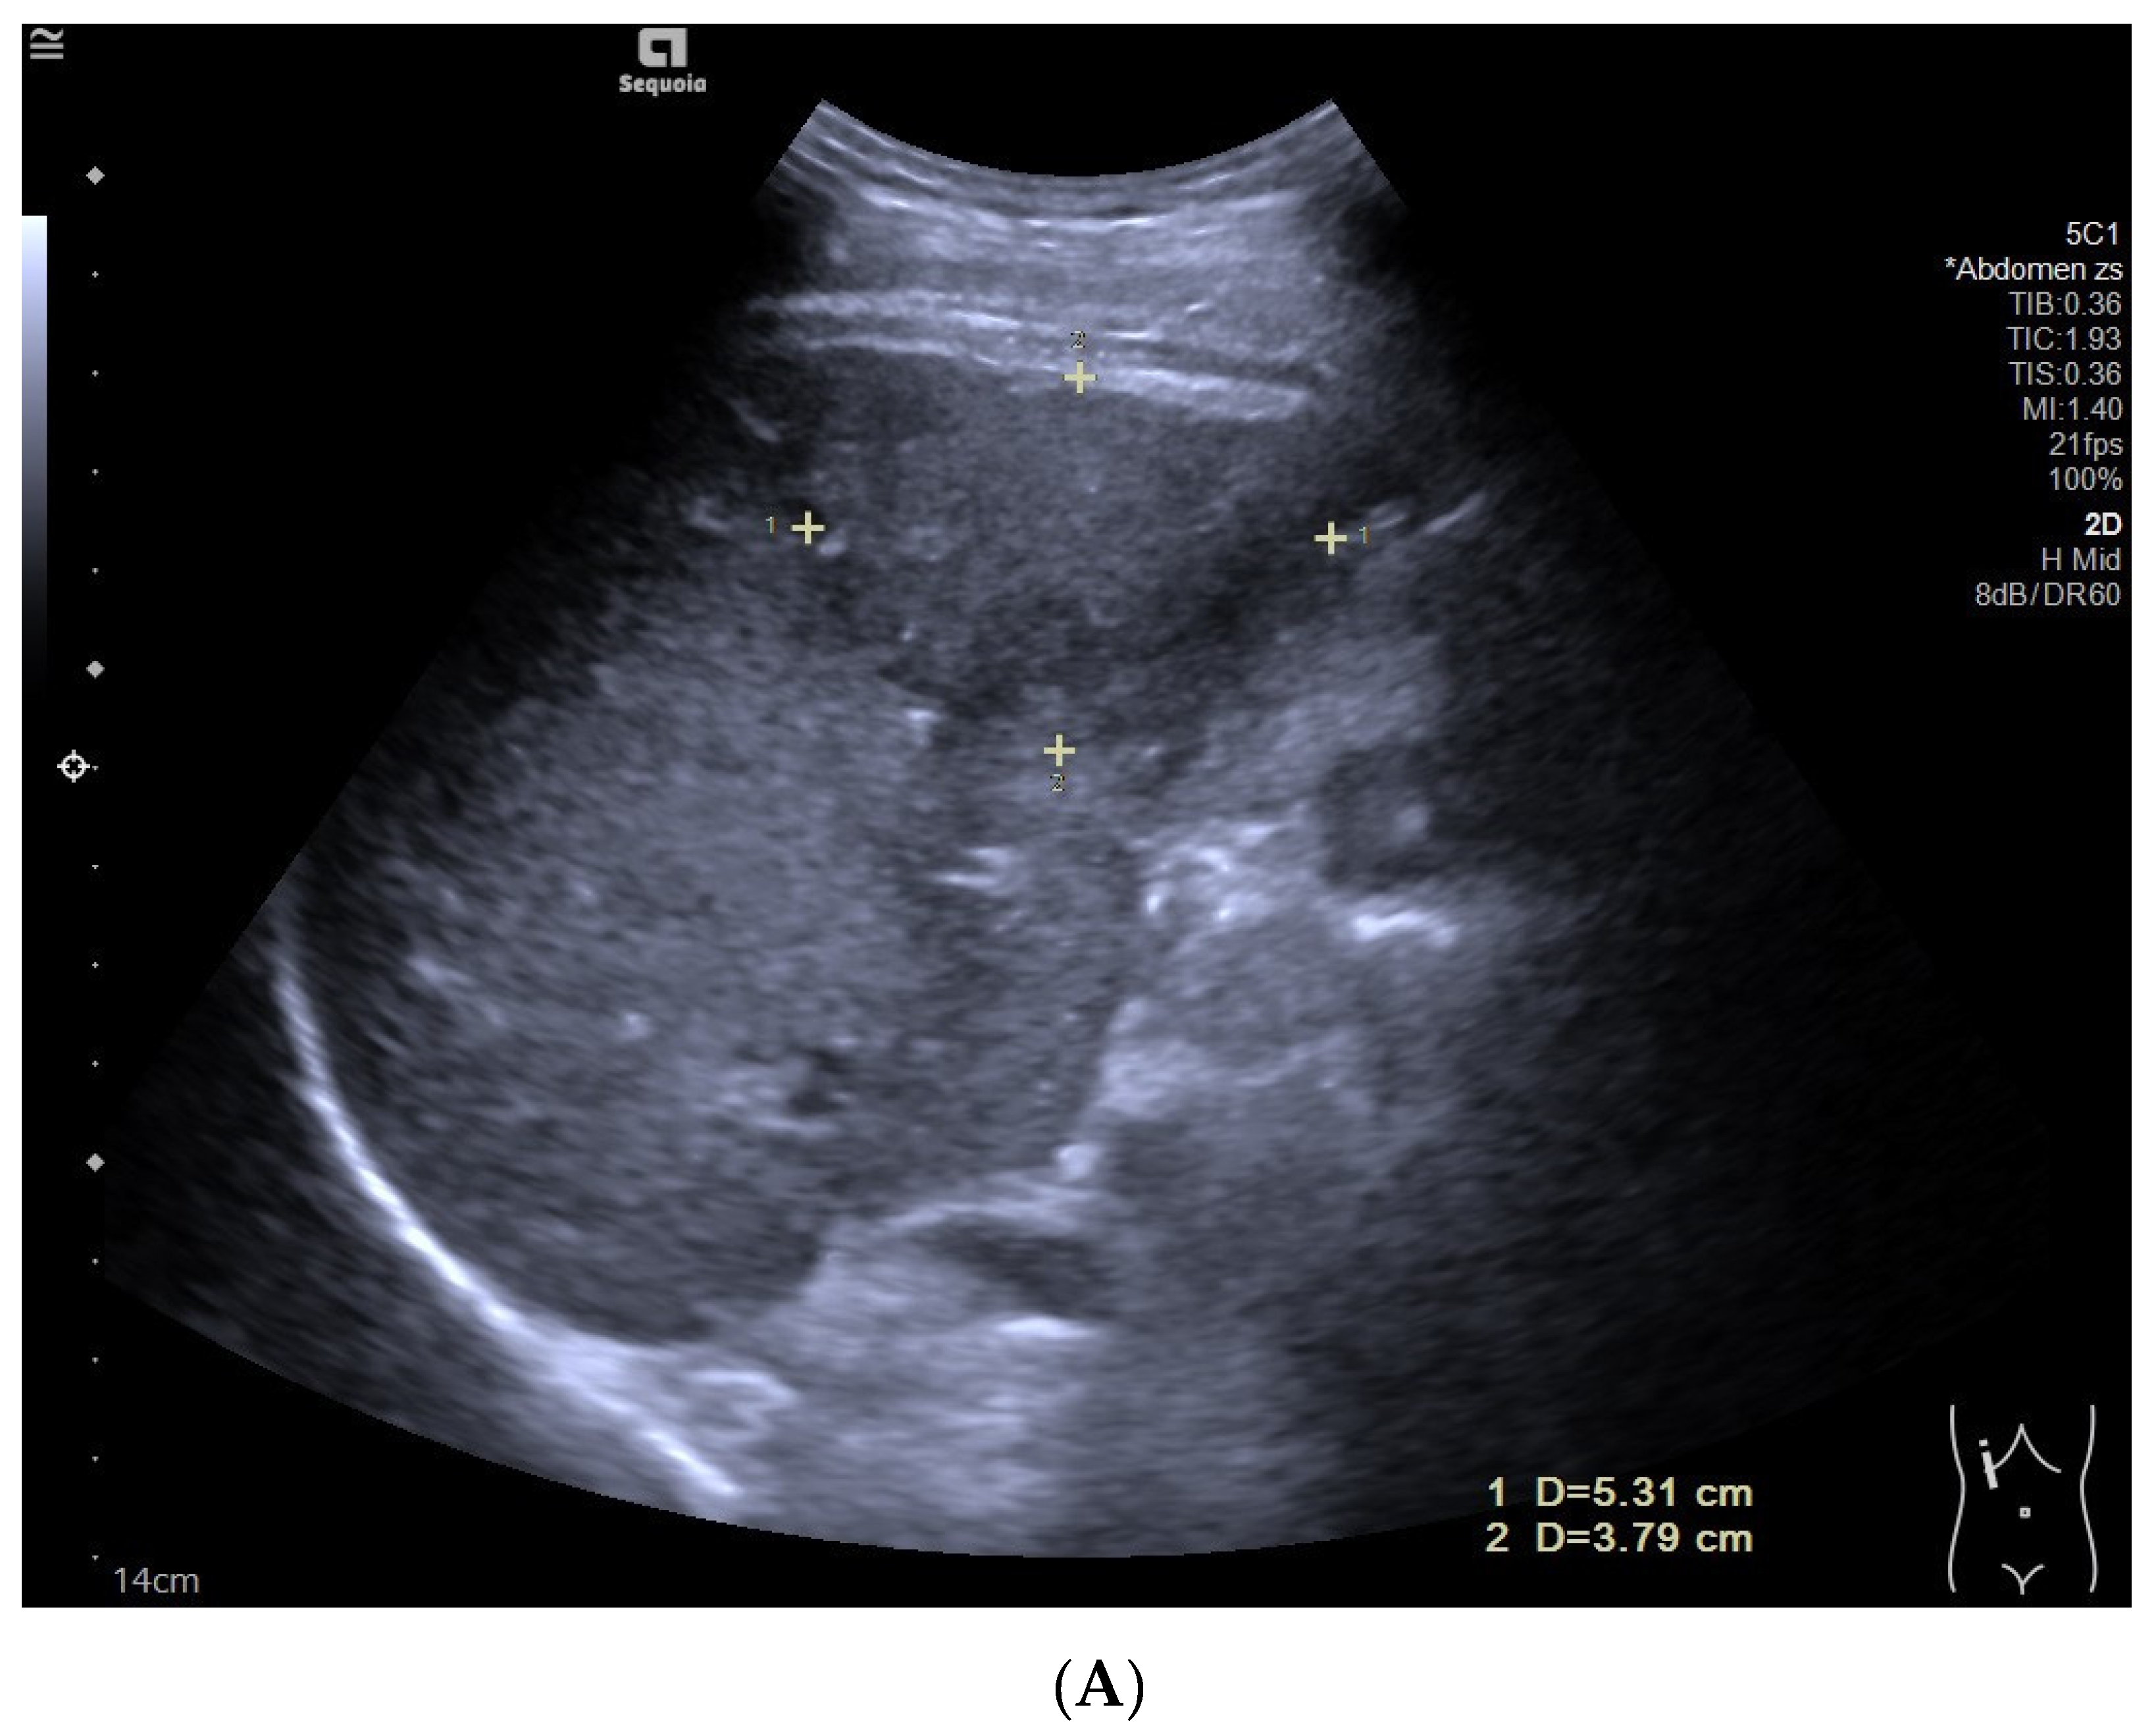

フィリップス、「Liver Fat Quantification(肝脂肪化定量評価。肝臓がん|消化器|診療内容|医療法人 甘木第一クリニック。肝臓がん|消化器|診療内容|医療法人 甘木第一クリニック。sakuraさん専用 蔵王吊るし柿4kg 紅干し柿 600g。Contrast Enhanced Ultrasound (CEUS) | フィリップスヘルスケア。Liver Ultrasonography | SpringerLink。キヤノンメディカルシステムズ、『肝臓の脂肪量の汎用超音波画像。Imaging Features of Hepatocellular Carcinoma in the Non。Imaging Features of Hepatocellular Carcinoma in the Non。714cFtk9QyL._AC_UF350,。肝臓病変における超音波の最新情報-第24回腹部放射線研究会。KMS_M01_XXX_670.jpg。腹部の超音波検査健康なヒト胆嚢 - 胆嚢のストックフォトや画像。